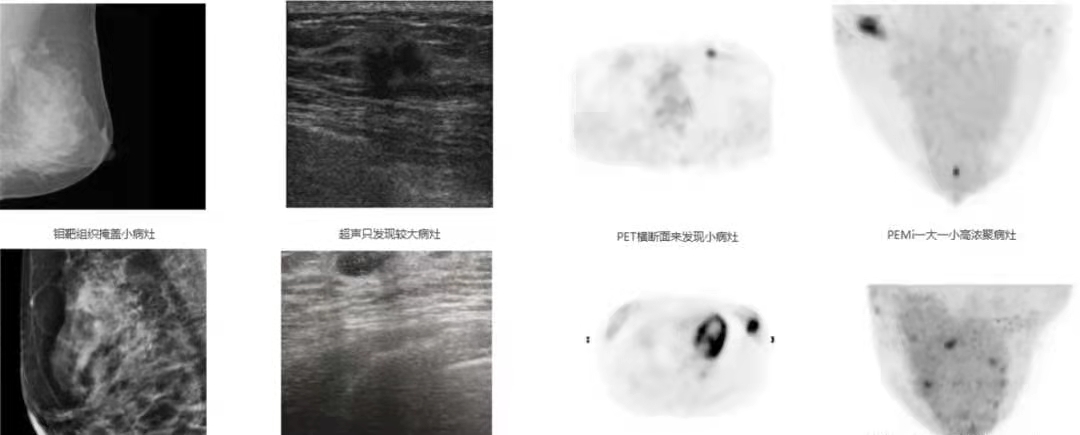

乳腺PET和超聲、鉬靶對比

根據臨床試驗合作醫院的研究:PEMi對于浸潤性導管癌、浸潤性小葉癌、浸潤性乳頭狀癌、葉狀腫瘤及其他特殊類型癌的診斷準確率較鉬靶、超聲高,PEMi還具有高分辨率、高靈敏度,對于乳腺小癌癥的診斷具有非常高的臨床應用價值;將PEMi與鉬靶、超聲聯合應用于診斷乳腺癌,可明顯提高診斷準確率(達98.8%),為早期診斷、早期治療提供了有效方法。